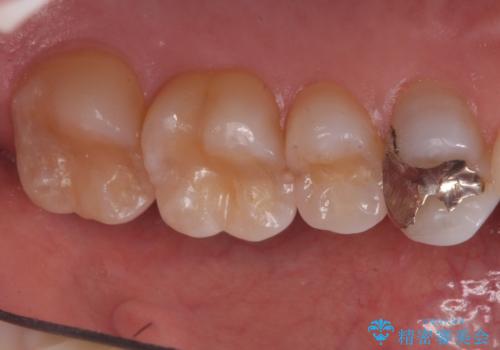

- 奥歯の詰め物のやり替え希望で来院されました。

残る歯の量が多かったためすべてインレーでの治療となりました。

- 左上4567 セラミックインレー 7,7000円×4本 費用は治療当時の料金となります